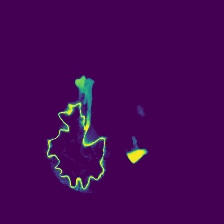

Diffusion models have shown impressive performance for generative modelling of images. In this paper, we present a novel semantic segmentation method based on diffusion models. By modifying the training and sampling scheme, we show that diffusion models can perform lesion segmentation of medical images. To generate an image specific segmentation, we train the model on the ground truth segmentation, and use the image as a prior during training and in every step during the sampling process. With the given stochastic sampling process, we can generate a distribution of segmentation masks. This property allows us to compute pixel-wise uncertainty maps of the segmentation, and allows an implicit ensemble of segmentations that increases the segmentation performance. We evaluate our method on the BRATS2020 dataset for brain tumor segmentation. Compared to state-of-the-art segmentation models, our approach yields good segmentation results and, additionally, detailed uncertainty maps.